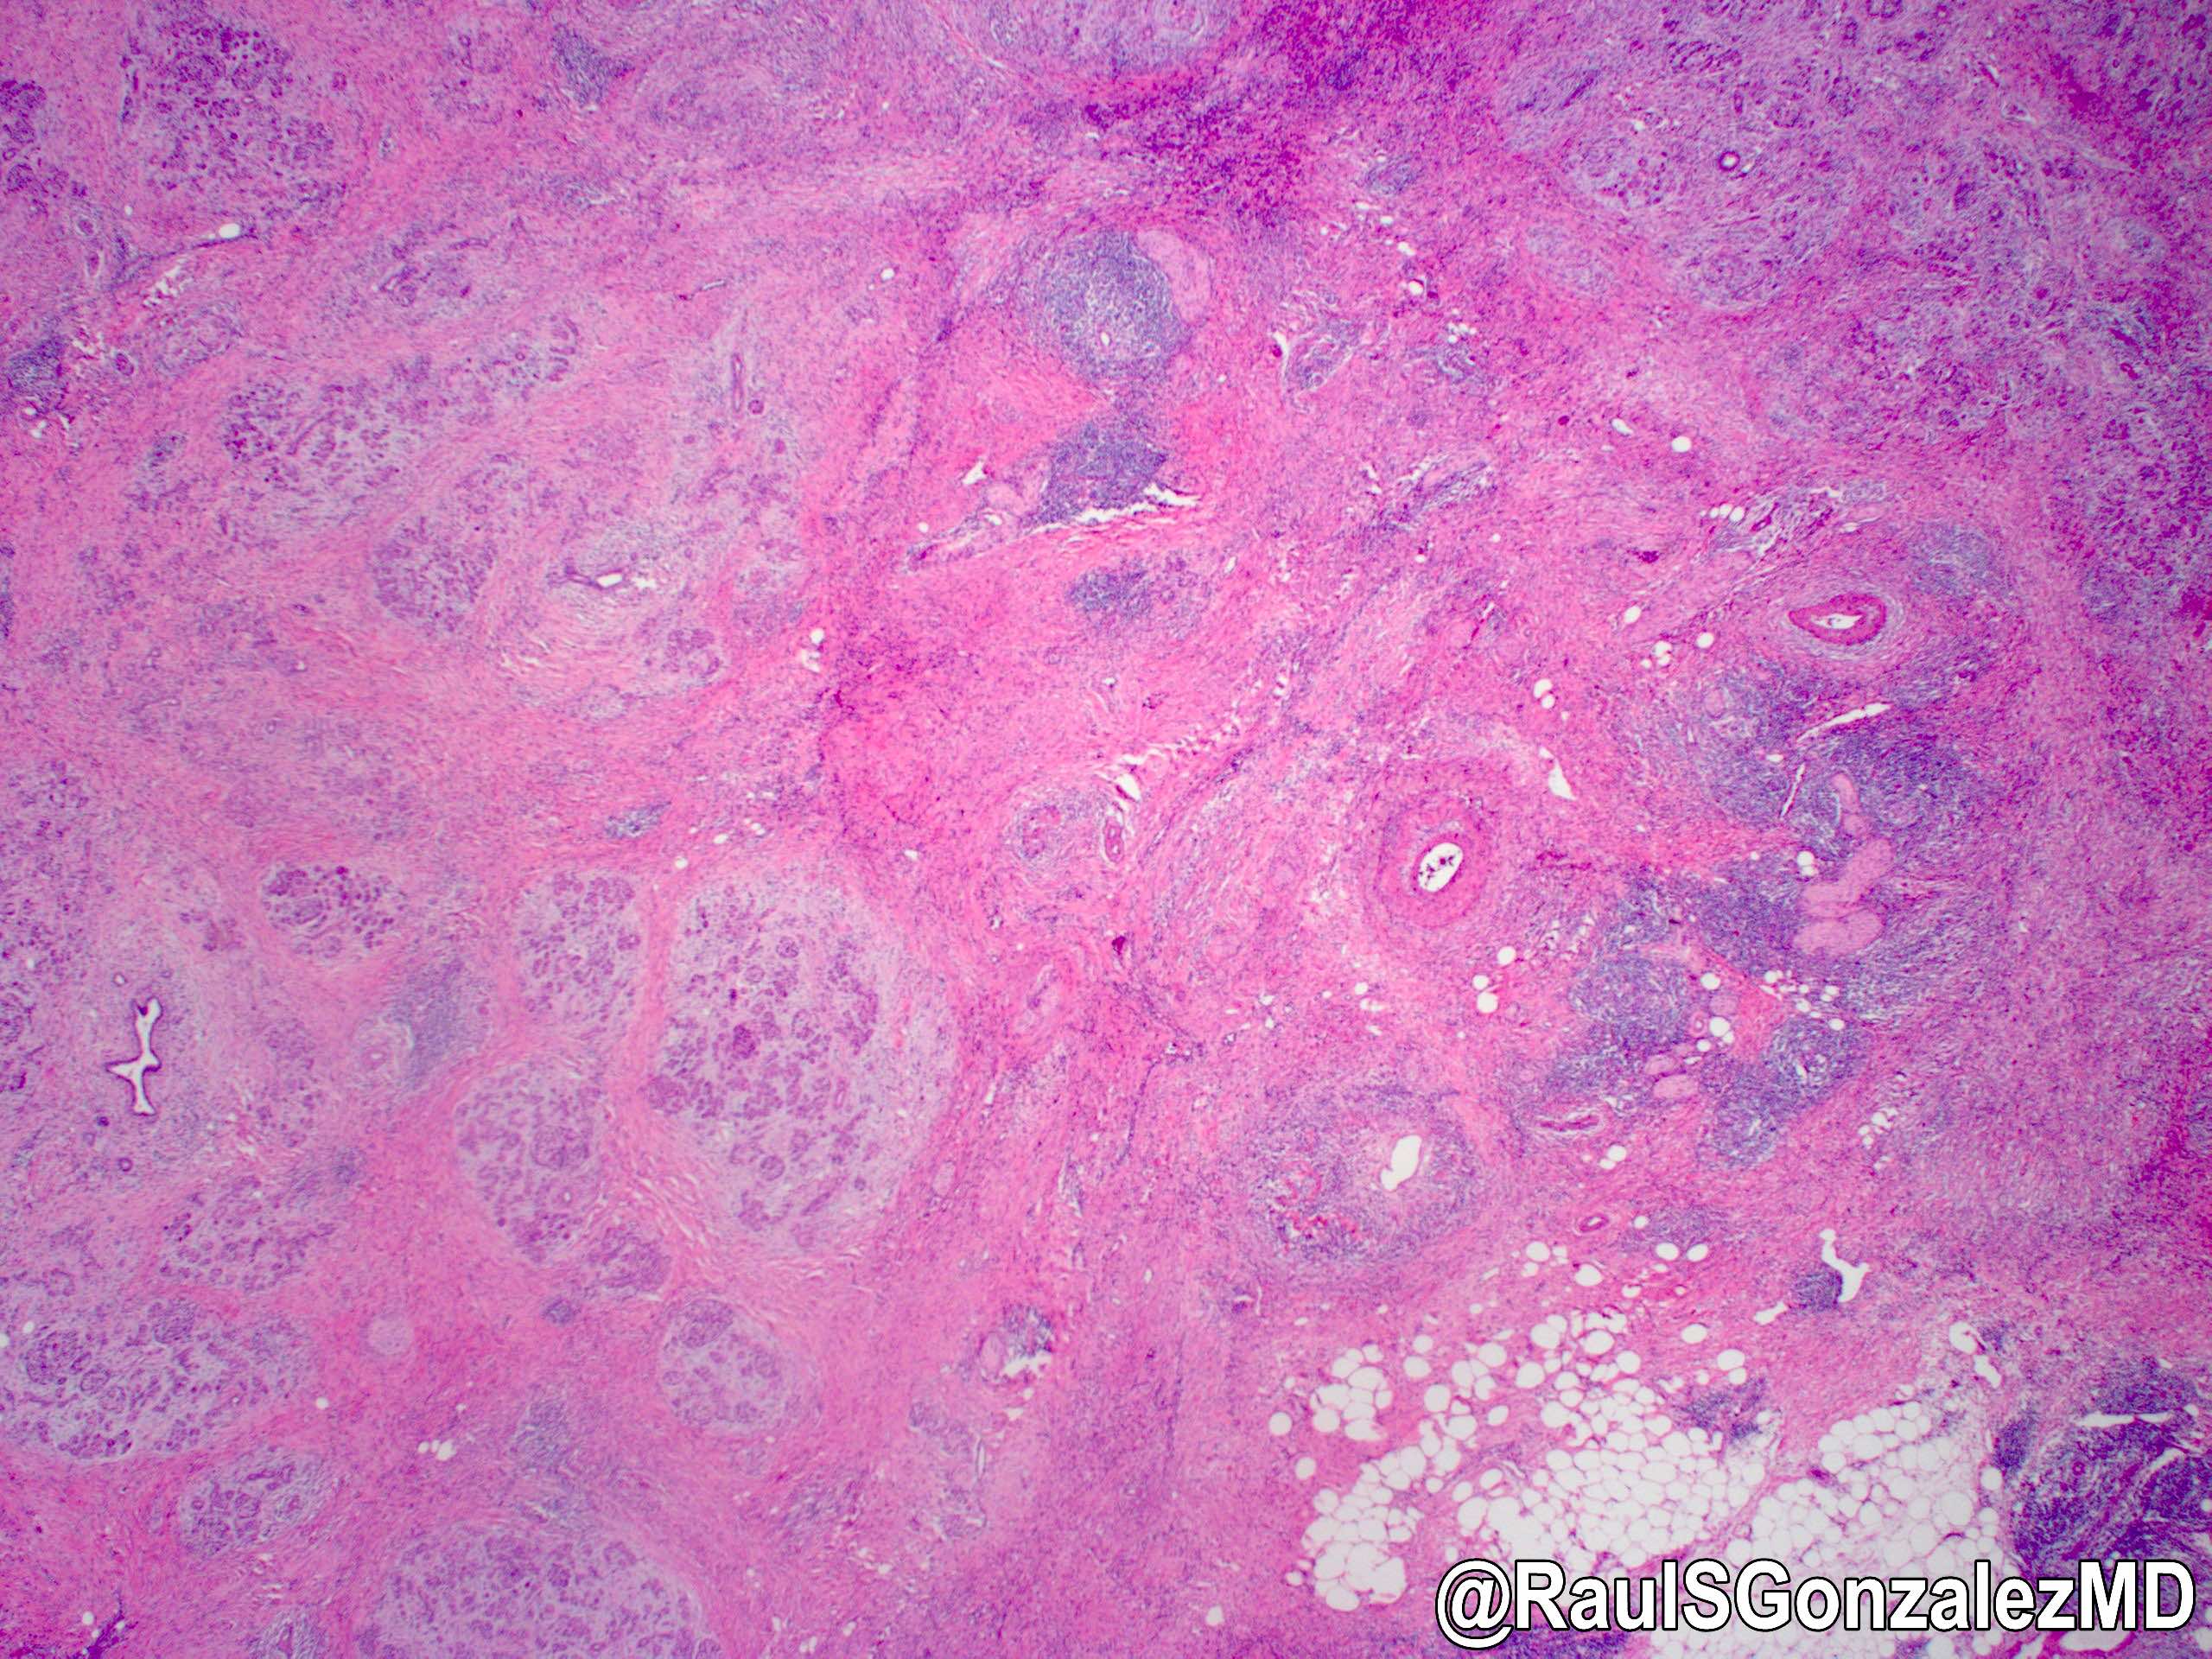

Microscopic (histologic) description

- Characteristic findings (at least 3 for level 1 criteria) (Pancreas 2011;40:352)

- Periductal lymphoplasmacytic infiltrate without granulocytic infiltration

- Obliterative phlebitis

- Storiform fibrosis

- Abundant (> 10 cells/high power field) IgG4 positive plasma cells

- Biopsy showing some but not all of the above features can be used as supportive evidence for the diagnosis of autoimmune pancreatitis (Pancreas 2011;40:352)

- Inflammation is localized within the pancreatic parenchyma and is centered around / within medium to large interlobular ducts, which causes shrinkage of the ductal lumen (Pathologica 2020;112:197)

- Inflammation can also be seen between the pancreatic parenchyma and peripancreatic adipose tissue (Pathologica 2020;112:197)

- Inflammation of the venous wall can progress to obliterative phlebitis with fibrosis of the lumen (Pathologica 2020;112:197)

- As the inflammation progresses, fibrosis becomes more diffuse, assuming a whorled or storiform pattern (Pathologica 2020;112:197)

- Perineural inflammation can also be present (Pathologica 2020;112:197)

- Involvement of the pancreatic neck margin or biliary resection margin should be clearly stated in the pathology report for therapeutic purposes (Pathologica 2020;112:197)

Microscopic (histologic) images